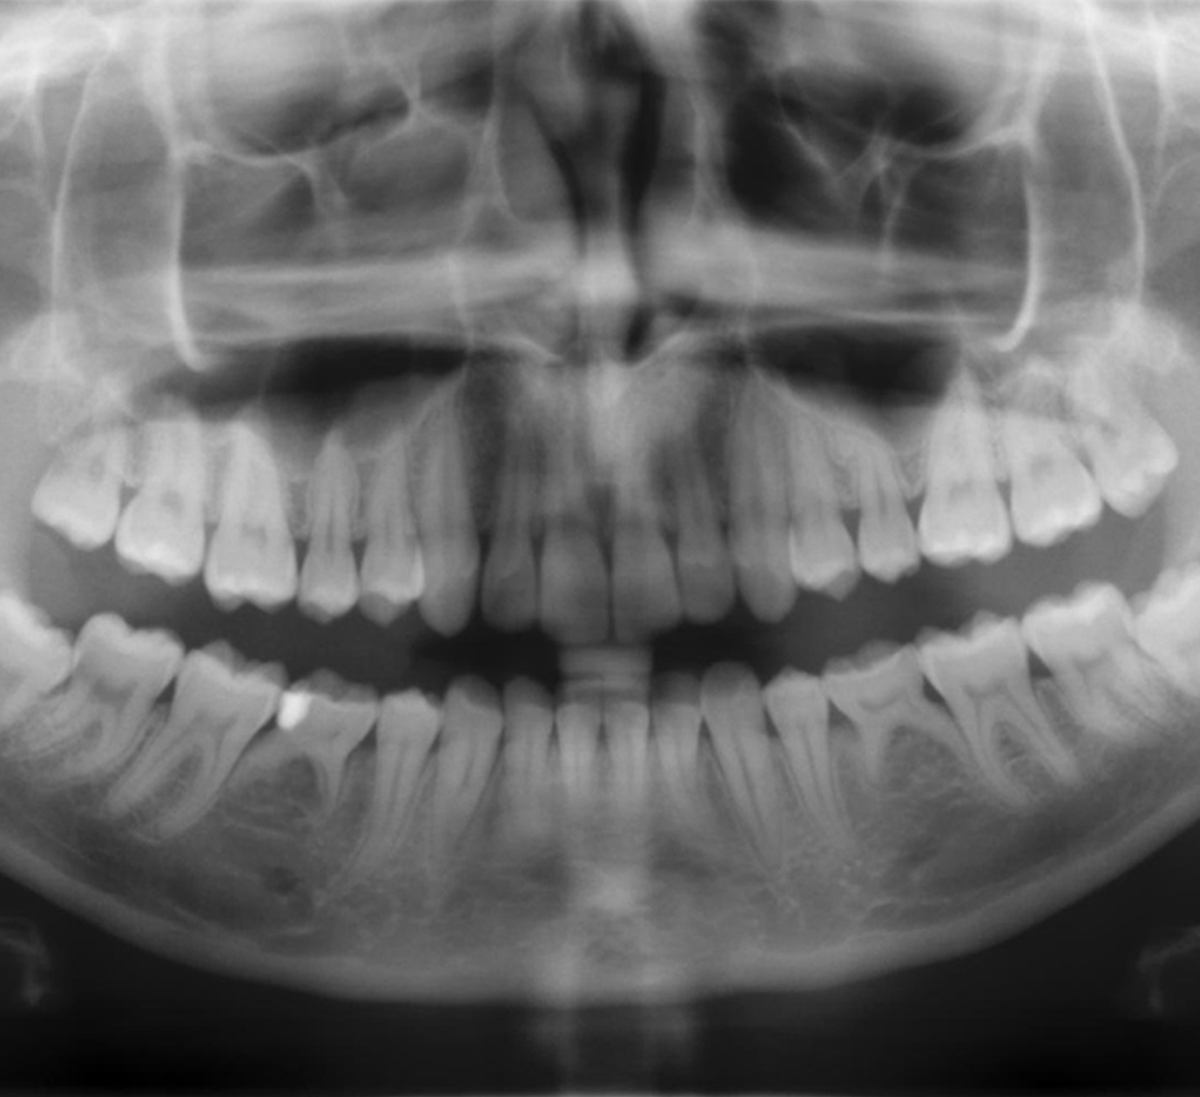

Die durch ein 3D-Bild gelieferte Datenqualität ist eine revolutionäre Kraft in der Dentaldiagnostik. Die Möglichkeit, überlagerte Zähne, unerwartete Kanäle und verdeckte Wurzeln zu visualisieren, erhöht die Genauigkeit und Aussagekraft bei der Diagnose eines Patienten. Ein besseres Verständnis und mehr Vertrauen wirken sich positiv auf die Akzeptanz der Patienten und den Behandlungserfolg aus.

Wenn es um Volumengröße, Dosis und Bildqualität geht, bringt jeder klinische Fall individuelle Anforderungen mit sich. Wählen Sie das geeignete Volumen für Ihren Bedarf: Vom fokussierten Ø 5 cm x 5,5 cm Volumen bis zum Ø 11 cm x 10 cm Volumen, das die Weisheitszähne und oberen Atemwege abbildet.